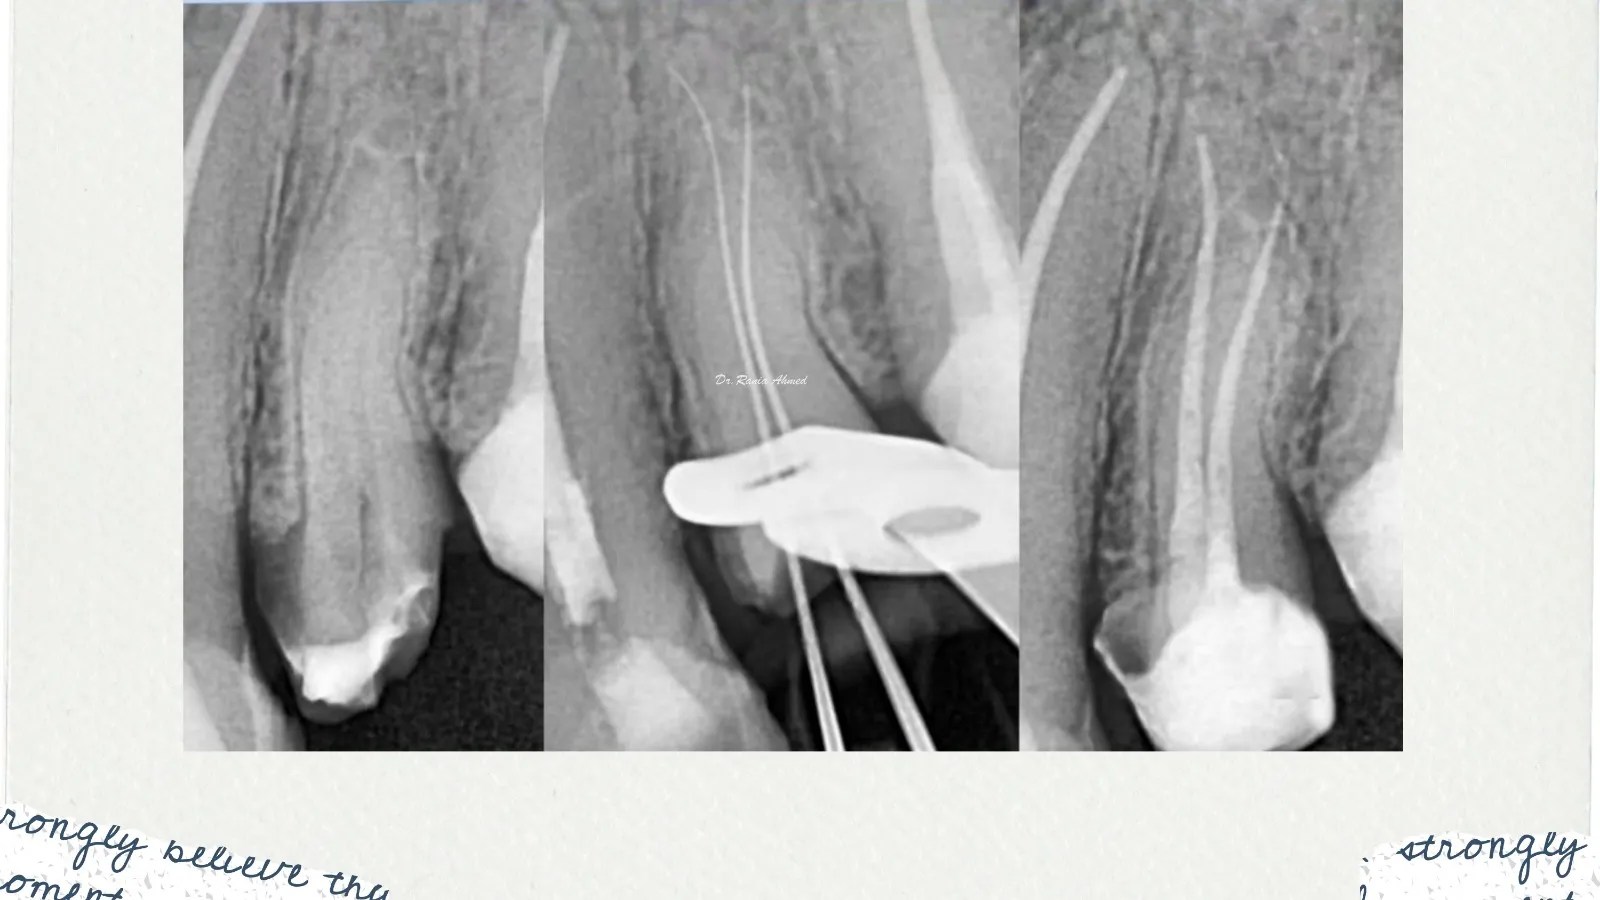

Endodontic Treatment